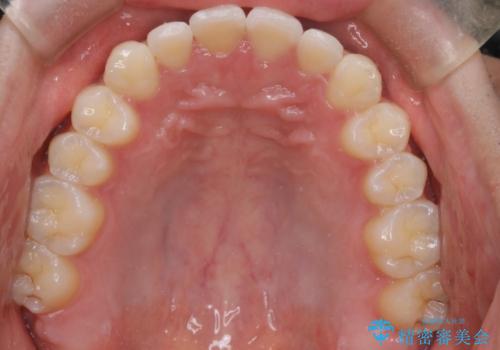

初診時の歯並びの状態としては、上下ともに前歯部の中等度以上のがたつき(叢生)があり、右の前歯が1本飛び出した状態でした。

抜歯は行わず上下顎ともに、主に歯列弓の拡大とディスキング(歯と歯の間に隙間を作る処置)を行い叢生を改善しました。

見た目、嚙み合わせ及び、治療期間や施術内容に大変ご満足いただきました。